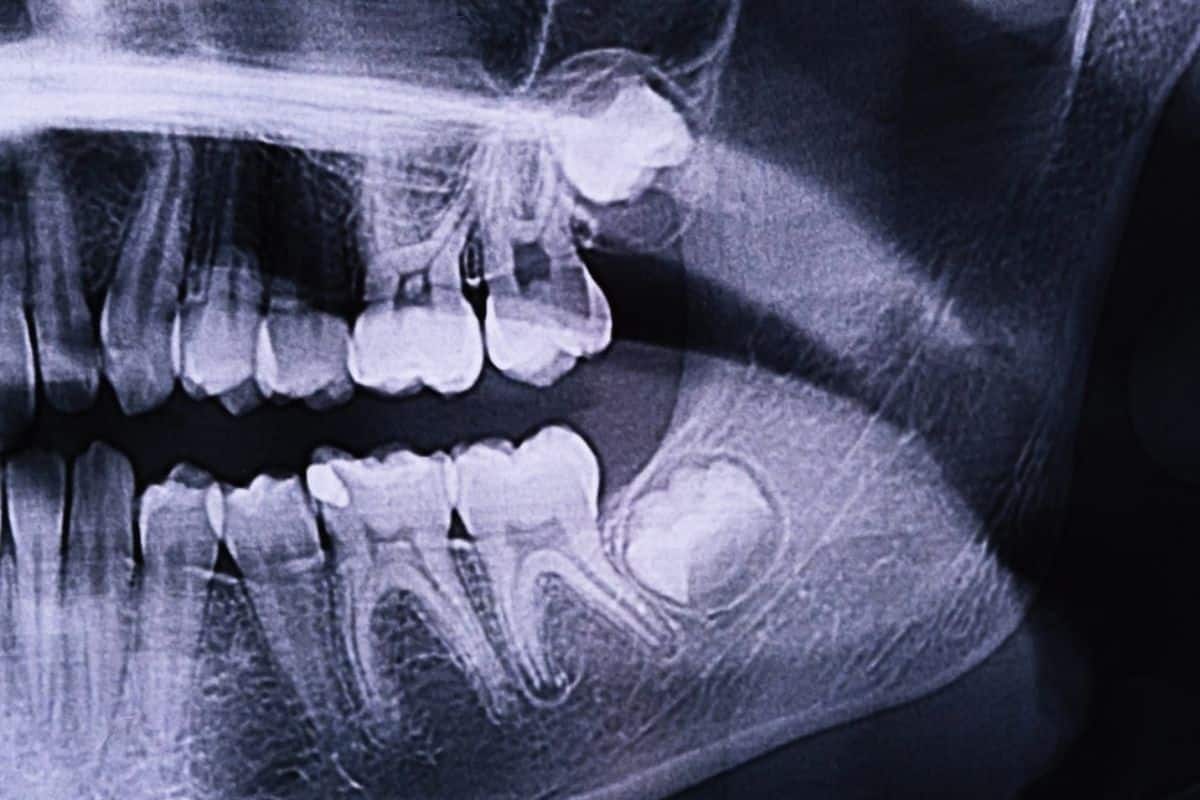

Your third set of molars, also referred to as wisdom teeth, might become impacted if they don’t emerge fully or correctly. A wisdom tooth infection can occur when a wisdom tooth erupts partially. It happens because in the opening area, bacteria forms since it becomes extremely difficult to clean.

A wisdom tooth infection, sometimes referred to as pericoronitis, is a dangerous condition that can be challenging to cure. This is due to the fact that a flap of gum will conceal the area where your wisdom teeth partially erupt. As long as this flap of gum remains, your wisdom tooth won’t come in fully. However, unless the wisdom teeth are extracted, the infection is not likely to clear up.